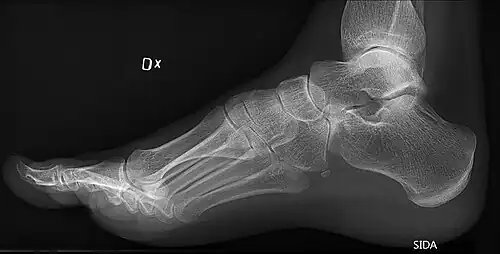

High arch in foot of a person with a hereditary neuropathy

Pes cavus, also known as high arch, is an orthopedic condition that presents as a hollow arch underneath the foot with a pronounced high ridge at the top when weight bearing.

This foot type is typically characterized with cavus—the elevation of the longitudinal plantar arch (e.g., the bottom arch of a foot), plantar flexion of the foot, forefoot pronation, hindfoot varus, or forefoot adduction. A high arch is the opposite of a flat foot and is somewhat less common.

On weightbearing projectional radiography, pes cavus can be diagnosed and graded by several features, the most important being medial peritalar subluxation, increased calcaneal pitch (variable) and abnormal talar-1st metatarsal angle (Meary's angle).[17] Medial peritalar subluxation can be demonstrated by a medially rotated talonavicular coverage angle.[17]